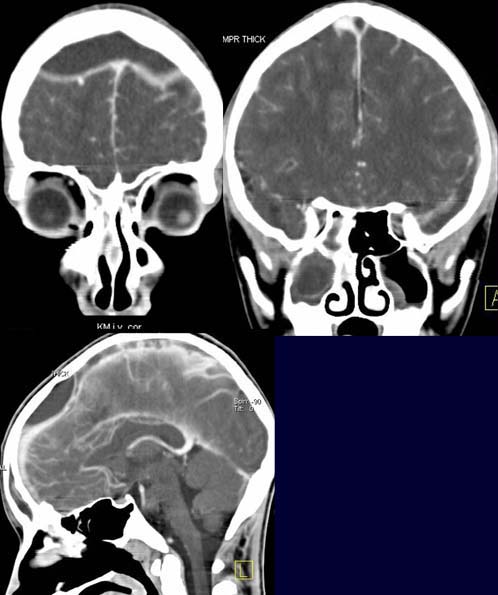

Epidurale und subdurale homogen hypodense Flüssigkeitsansammlungen mit

starkem randständigen Kontrastmittel-Enhancement.

In der sagittalen und coronaren MPR Kontrastmittelausspaarung im

Sinus sagittalis superior.

Schleimhautschwellung und Flüssigkeitsansammlung mit

Spiegelbildung in den Nasennebenhöhlen.